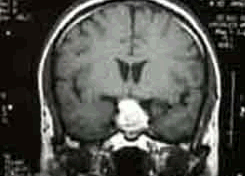

4.MRI檢查MRI對顯示鞍上小的生殖細胞瘤(直徑<1cm)或脊髓轉移灶十分清楚;顯示松果體區生殖細胞瘤常為圓形、橢圓形或不規則形多數T1為等或稍低信號,T2為稍高信號,少數亦可為等信號;注藥後均勻一致的強化,邊界清楚有時少數僅呈中度或不均勻強化有報告20%-58%的生殖細胞瘤有小的囊變,這些囊變由於蛋白性液體或壞死液化所致,通常極小,有時在瘤內有小出血灶,在T1像為高信號;松果體區者可侵犯中腦和丘腦在T2像上有周邊模糊高信號影。MRI對腫瘤的種植或播散顯示全面除了T1及T2像的多發病灶顯示清晰而注藥後病變明顯強化。底節生殖細胞瘤也是T1等或低信號而T2稍高信號,注藥後可均勻強化有的顯示同側皮層有萎縮現象。